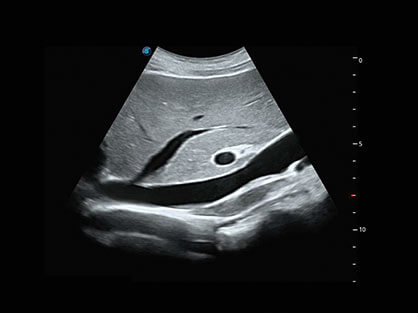

0.5mm厚度的薄层切片显像,可清晰显示微小病灶的连续断面。

可同时显示组织结构表面和内部的轮廓信息,达到透视效果,为临床提供更丰富的诊断信息。